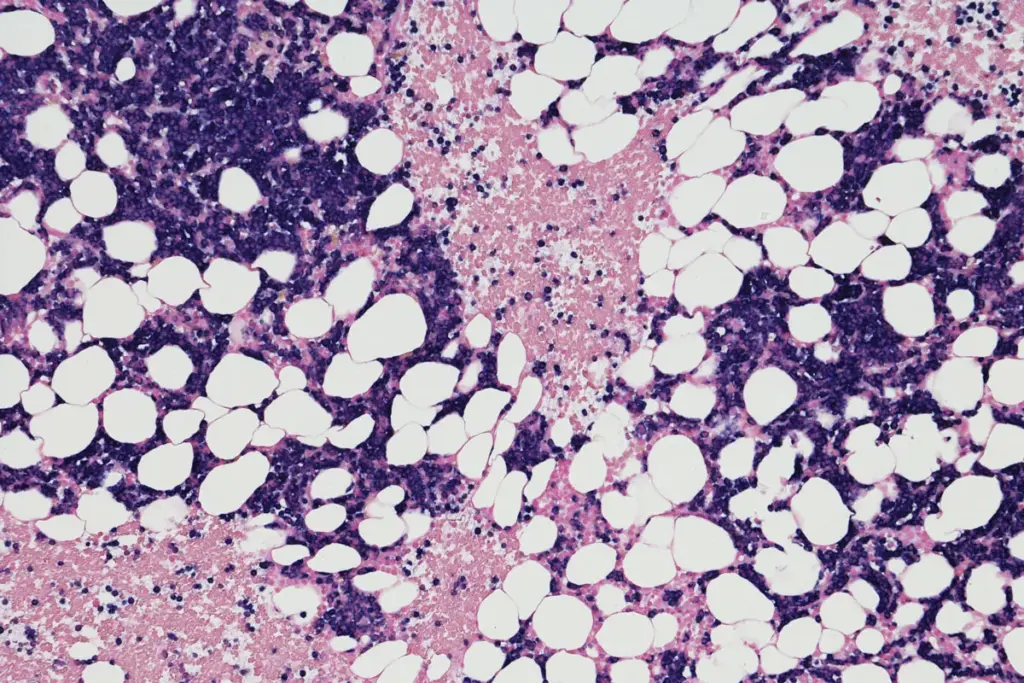

The overview and definition of multiple myeloma provides essential insight for patients, families, and healthcare professionals seeking clear information about this complex blood cancer. Multiple myeloma is a malignant disease of the plasma cells—a type of white blood cell that normally produces antibodies. When these cells become cancerous, they proliferate in the bone marrow, disrupting normal blood formation and leading to a range of systemic complications.

Multiple myeloma is a cancer that originates in the plasma cells of the bone marrow. These abnormal cells multiply uncontrollably, producing excessive monoclonal immunoglobulin (often called M‑protein) that can be detected in blood or urine. The disease typically progresses through several stages, from asymptomatic monoclonal gammopathy of undetermined significance (MGUS) to overt symptomatic myeloma.

• Bone Marrow Biopsy: Determines plasma‑cell percentage and cytogenetics.